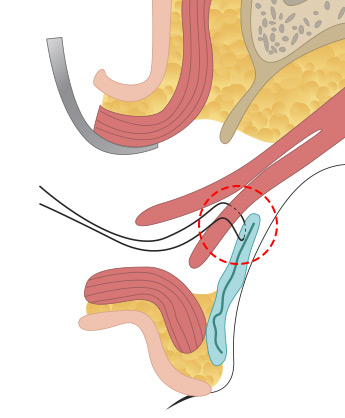

근육과 근막이 안검판이라는 조직에 붙어 있는데 안검하수의 정도에 따라서 경미한 경우는 근막의 길이를 축소해서 다시 붙여주는 상안검거근막 수술을 해주고, <br>

중증도의 경우 뮬러 근육을 당겨서 안검판에 고정하는 수술을 하고 중증인 경우에는 상안검거근을 아래로 당겨서 축소해주는 수술을 합니다.

올림근 널힘줄 중첩술

올림근 널힘줄 중첩술

올림근 널힘줄 중첩술 -

뮬러근 중첩술

뮬러근 중첩술 -

뮬러근 전진술

뮬러근 전진술 -

뮬러근과 올림근, 널힘줄을

뮬러근과 올림근, 널힘줄을

동시에 전진술로 교정